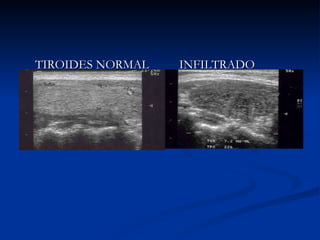

CRÓNICAS TIROIDITIS DE HASHIMOTO LABORATORIO: ANTI TG: + 60% ANTITPO: + 90% T4 bajo o normal T4 L baja o normal TSH alta o normal CENTELLOGRAMA:  No es útil Captación normal o aumentada ECOGRAFIA: No es útil Patrón hipoecogénico difuso

TIROIDES NORMAL INFILTRADO  PUNTIFORME

FIBROSIS EN BANDA